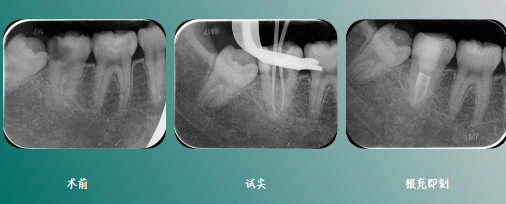

试尖

根充后髓腔内状态

影像学检查